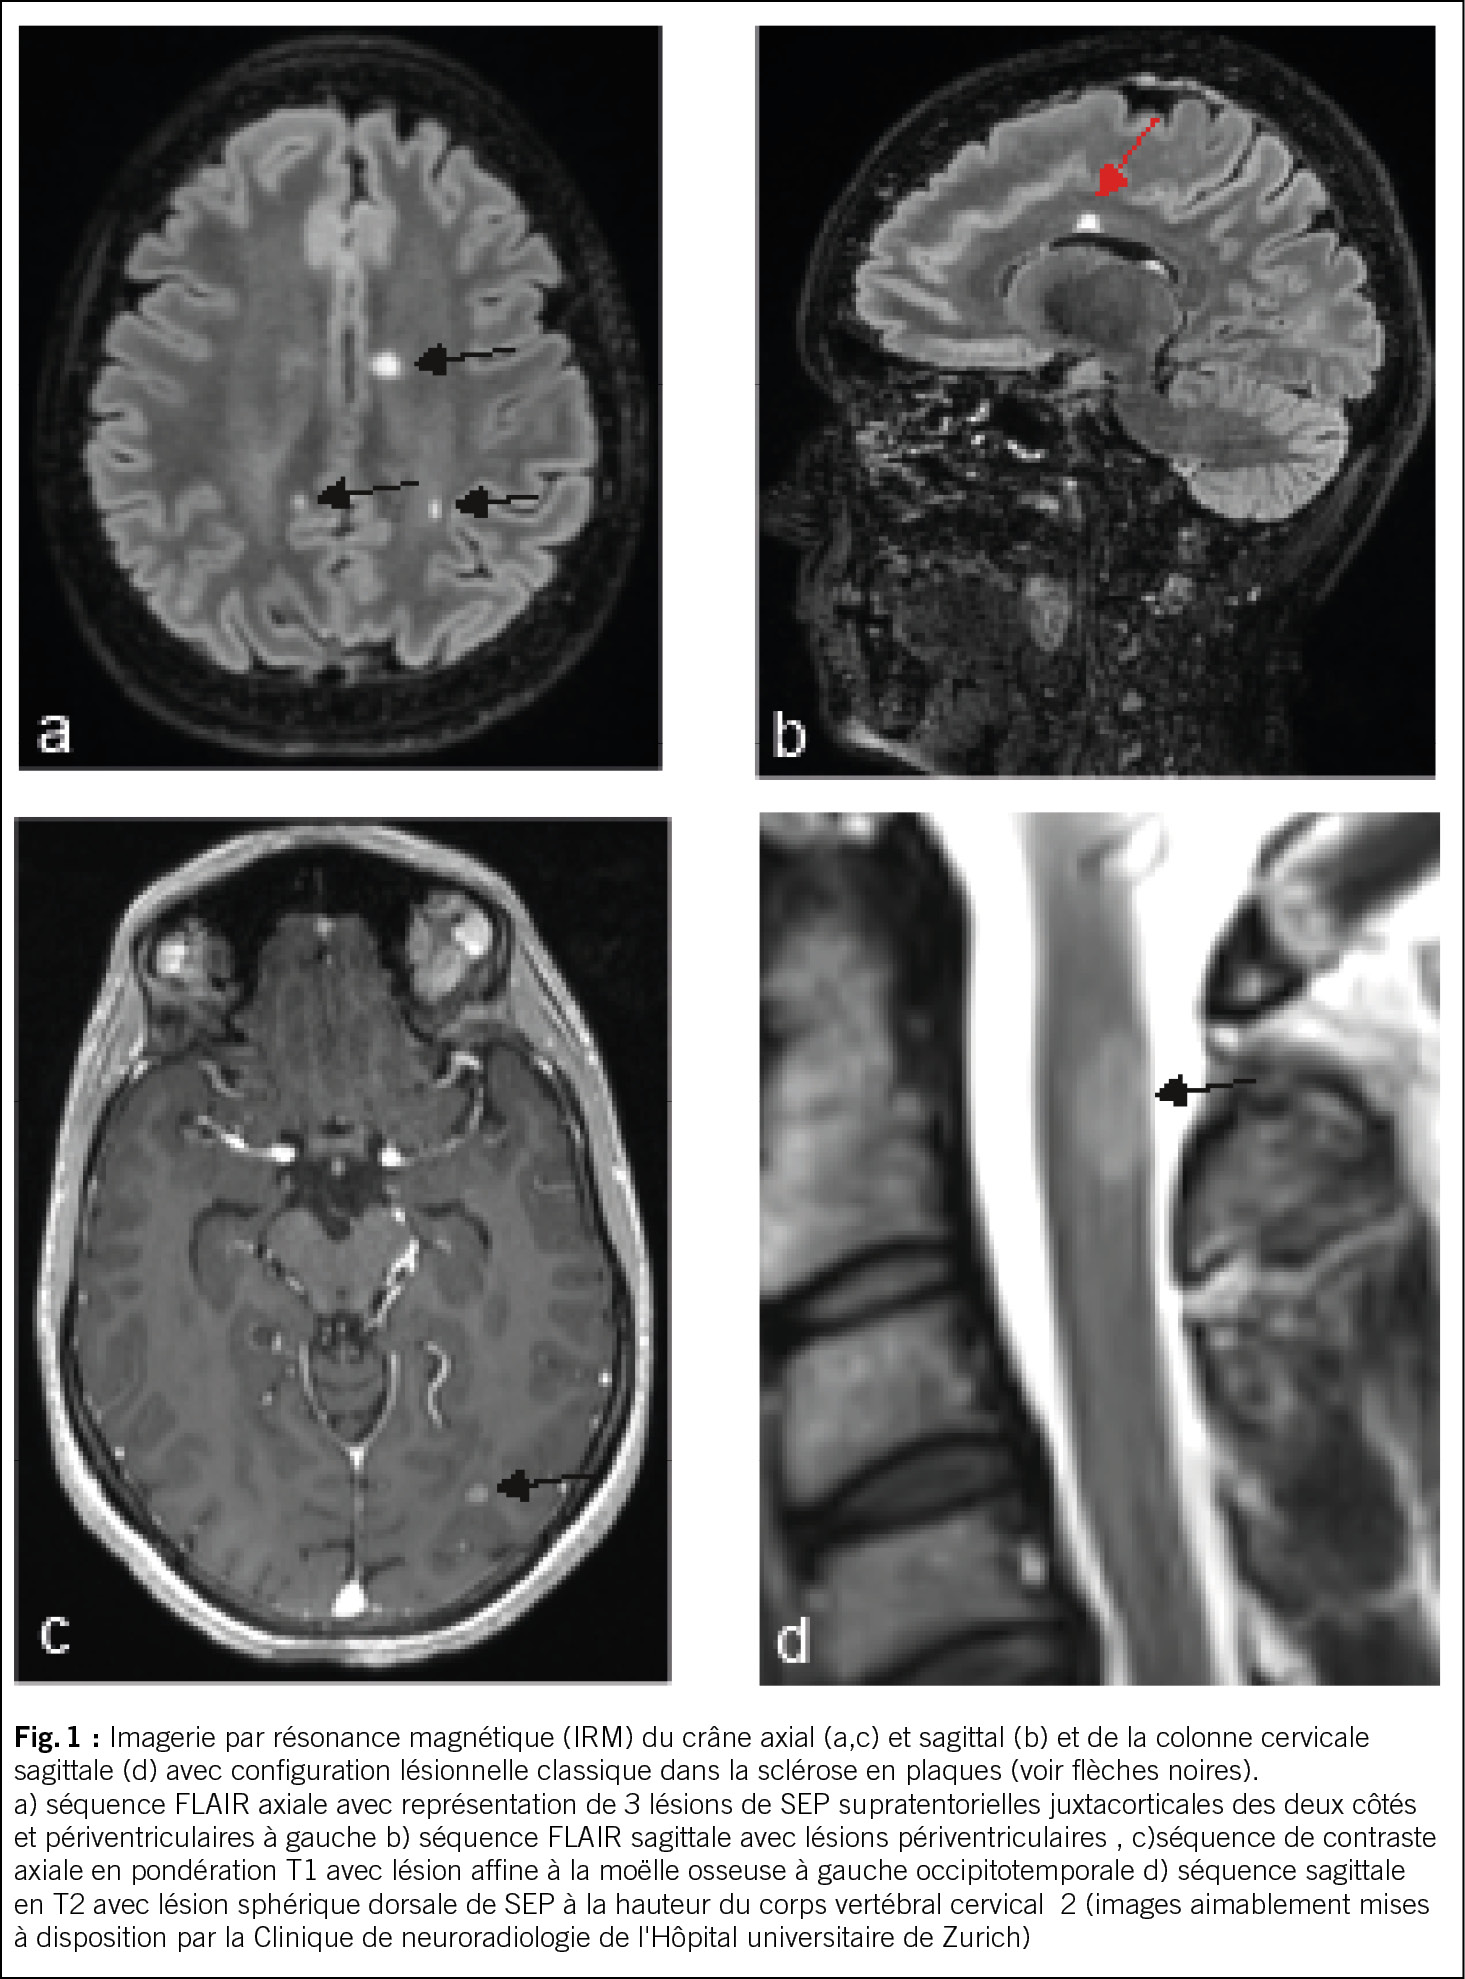

Dans un premier temps, après une anamnèse détaillée et un examen clinique neurologique, il convient, si la suspicion persiste, de procéder à une IRM avec produit de contraste du crâne ou, selon les symptômes, de la moelle épinière, en posant la question des modifications inflammatoires chroniques. Les quatre localisations classiques des lésions de SEP, généralement ovales, aux limites relativement nettes, puis confluentes, sont juxtacorticales, périventriculaires, infratentorielles et spinales (voir figure 1). Les lésions inflammatoires actives se distinguent par leur prise de contraste (4).